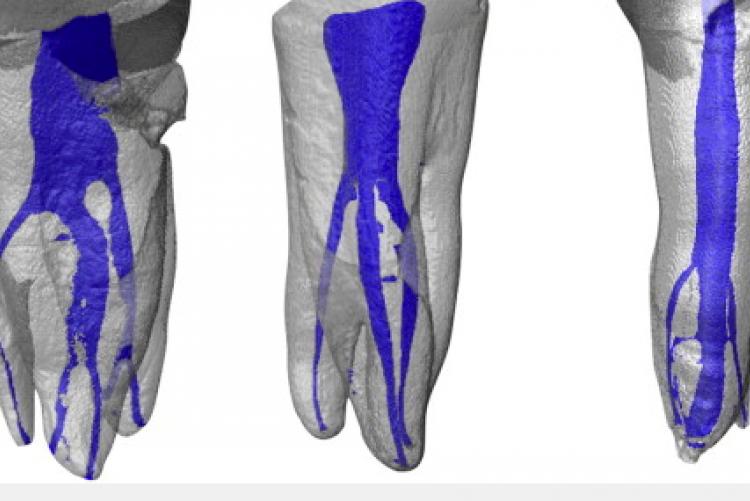

Conventional intra-oral radiography provides clinicians with cost-effective, high-resolution imaging that continues to be the front-line method for dental imaging. However, it is clear that there are many specific situations where the 3-D images produced by CBCT facilitates diagnosis and influences treatment. The usefulness of the CBCT cannot be disputed. It is a valuable task-specific imaging modality, producing minimal radiation exposure to the patient and providing maximal information to the clinician.